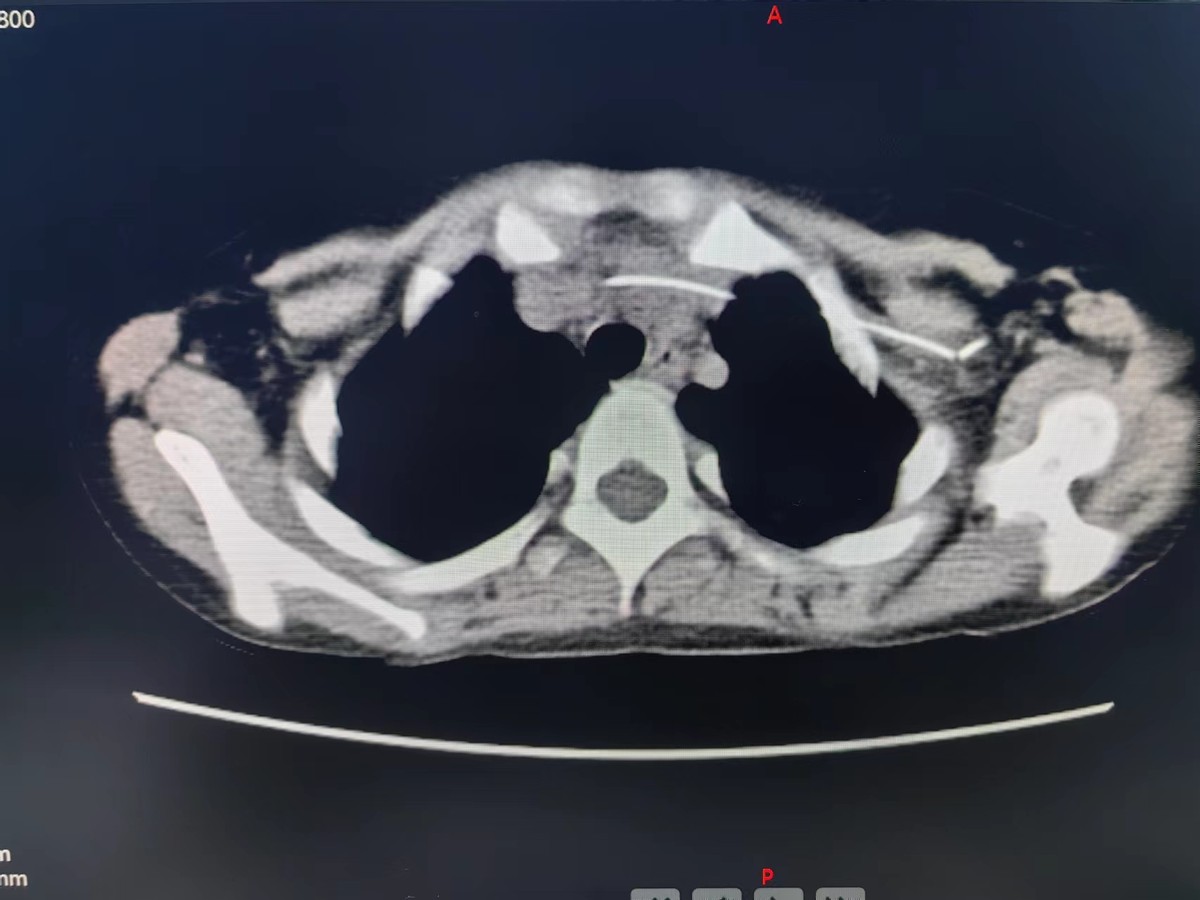

术前CT及胸片显示腋静脉段导管(箭头示)弯折断裂。

随后复查CT及三维重建显示:导管断裂,远端漂移至右下肺动脉。